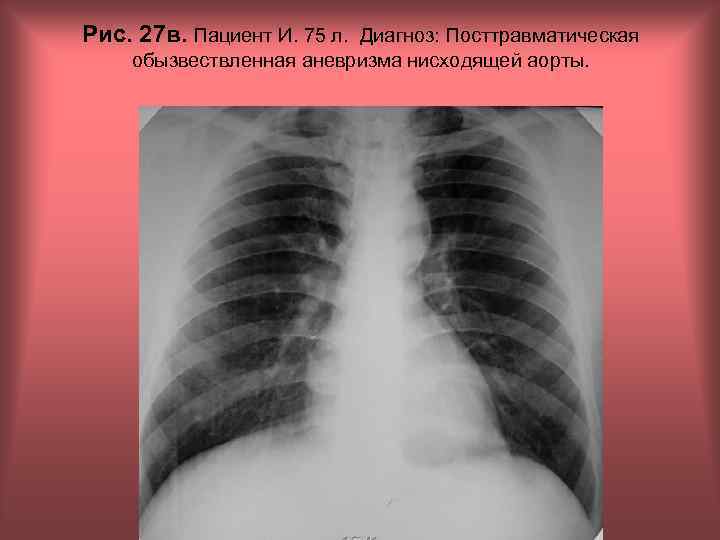

Рис. 27 в. Пациент И. 75 л. Диагноз: Посттравматическая обызвествленная аневризма нисходящей аорты. Н. С. Воротынцева, С. С. Гольев Рентгенопульмонология